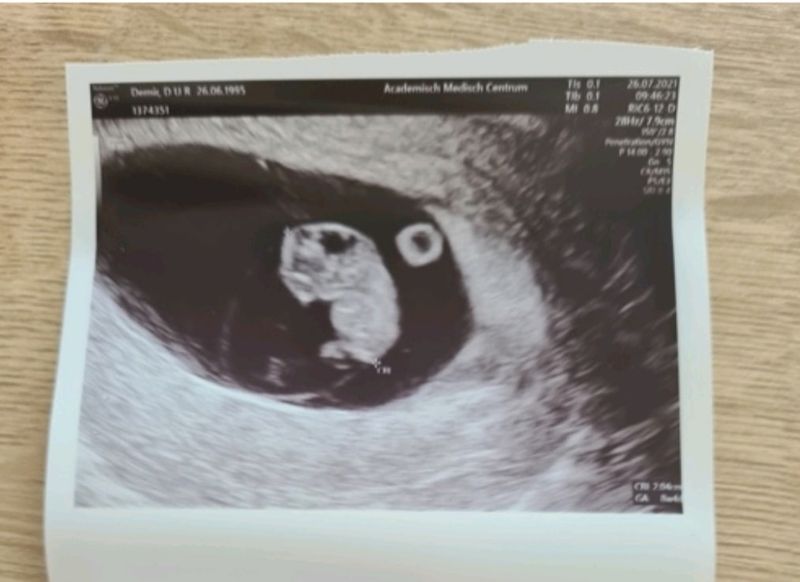

Vorig jaar kwam ik er op 20 juni 2021 achter dat ik weer zwanger was. Ik was ontzettend blij met mijn positieve zwangerschapstest. Vanwege mijn medische achtergrond mocht ik al vanaf zes weken een vroege echo, zodat we met zekerheid wisten of het om één baby of een meerling ging. We zagen een zeer mooie zwangerschap op de echo. Toen ik zeven weken en drie dagen was mocht ik bloed laten prikken bij het AMC. Zo konden we al vroeg zien wat voor geslacht ik droeg, zodat wij belangrijke afspraken konden inplannen. Als ik weer een meisje zou krijgen, dan zou er geen verder onderzoek nodig zijn, dan konden we hierbij laten. Als ik een jongetje zou krijgen, dan werd er verder onderzoek gepland, zoals een vlokkentest. De uitslag zou een paar weken duren. Mijn telefoon rinkelde en mijn hartslag ging meteen omhoog. Ik durfde niet op te nemen. Toch nam ik de telefoon op. Ik hoorde dat ik een zoontje zou krijgen. Ik huilde. Ik vond het meteen erg spannend.

Op 18 augustus had ik de vlokkentest. Ik was toen precies 12 weken zwanger. De vlokkentest vond ik geen enkel probleem. Ik was ontspannen en ik voelde totaal geen pijn. Ik had hierna ook geen bloedverlies. De uitslag van de vlokkentest kon 1 tot 3 weken duren. We wilden graag de uitslag weten voordat wij naar Turkije op vakantie zouden gaan. Binnen een week kreeg ik de uitslag. Ik nam op en de mevrouw aan de telefoon zei: “Ik ga je meteen blij maken. Uit de vlokkentest is geen Duchenne gebleken. Uw zoon is gezond.” Huilend van blijdschap belde ik direct mijn man op. Hij wist niet wat er hem over kwam. Ik huilde zo hard dat hij mijn niet goed kon verstaan. Hij dacht in eerste instantie dat er een slechte uitslag was, maar het was helemaal goed. We vierden het toen hij thuiskwam. Nu konden we met een gerust hart op vakantie toe gaan en shoppen voor ons kleine zoontje.